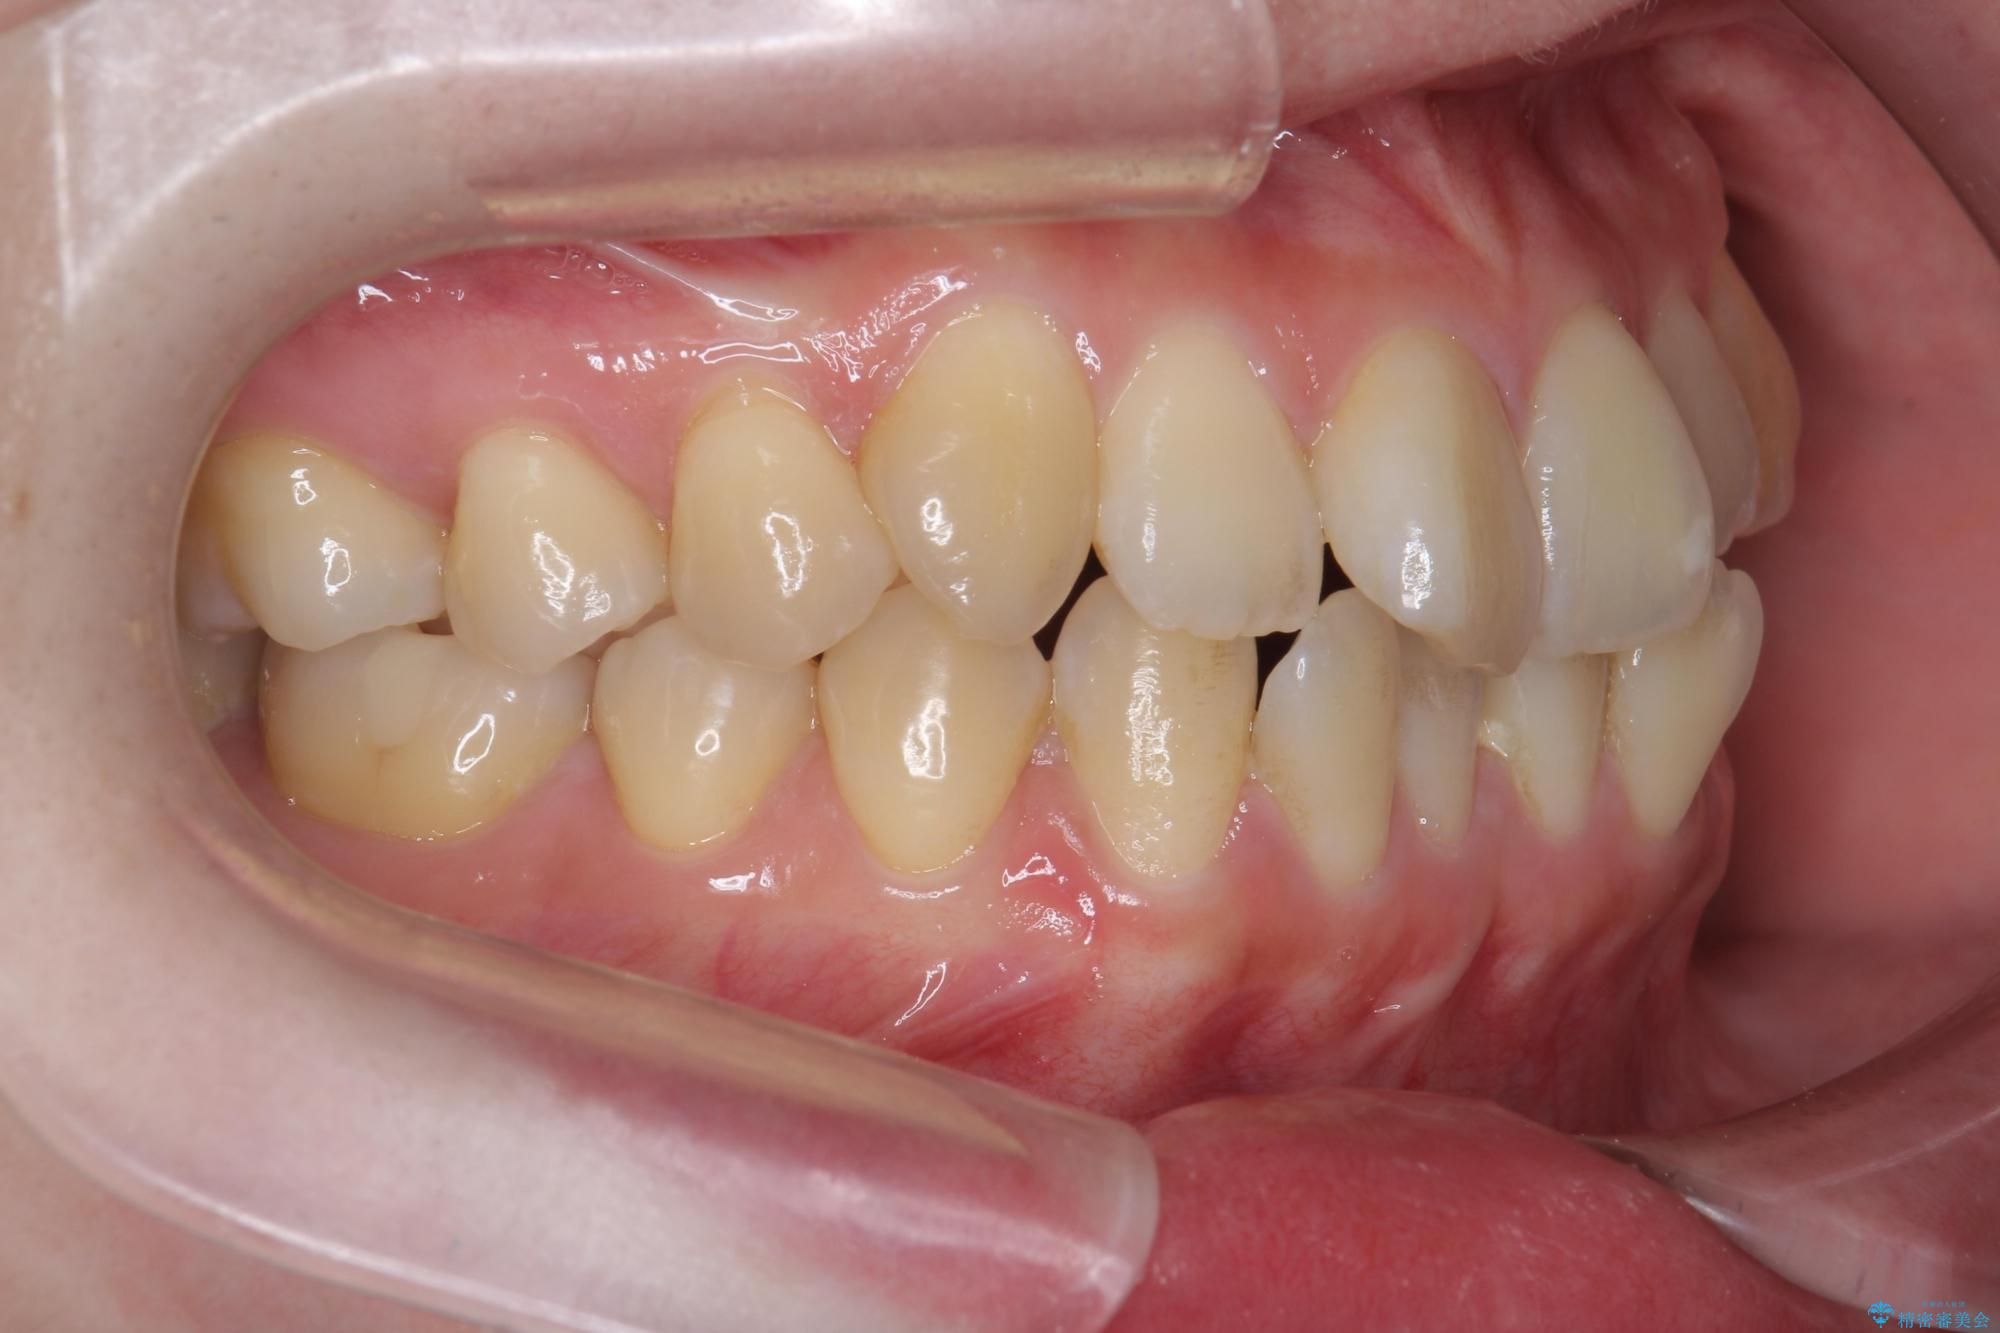

前歯のねじれが気になる、歯並びを改善したいとご来院された患者様です。

歯のねじれをきれいに取るのは、インビザライン(マウスピース矯正)だけでは難しい動きです。そのため、事前に4か月間の部分ワイヤー矯正を行い、治療期間を短くし、より美しい仕上がりを目指す計画です。

前歯が綺麗に並び、大変ご満足いただけました。